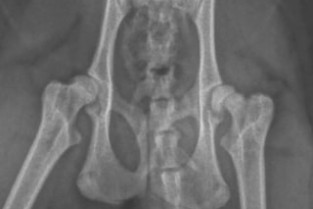

L'objectif pédagogique de ce cours avancé est de renforcer les connaissances en pathologie ostéo-articulaire chez le chat, qui représente une proportion importante des patients traités. Les spécificités anatomiques pertinentes de l’appareil musculo-squelettique du chat seront mises en avant ainsi que les techniques de traitement appropriées (focus sur les implants et les challenges rencontrés). L'accent sera toujours mis sur le côté pratique et visuel. Un temps important sera consacré à la discussion après chaque cours. Le succès des "cas cliniques interactifs" a conduit à leur accorder une part importante dans le programme de ce cours.

- Reconnaitre les principales maladies orthopédiques du chat

- Connaître les spécificités anatomiques en orthopédie féline

- Déterminer les principes de traitement dans les affections orthopédiques du chat